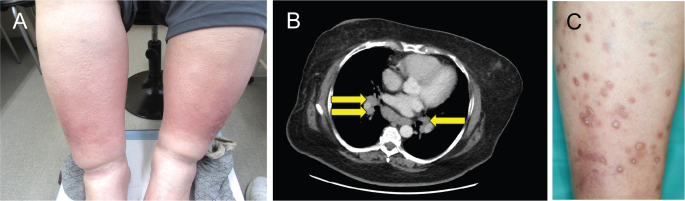

Löfgren's Syndrome Following BNT162b2 mRNA COVID-19 Vaccination and Subsequent Plaque-type Cutaneous Sarcoidosis after its Resolution.

BNT162b2 mRNA COVID-19疫苗接种后的Löfgren综合征和随后的斑块型皮肤结节病解决后